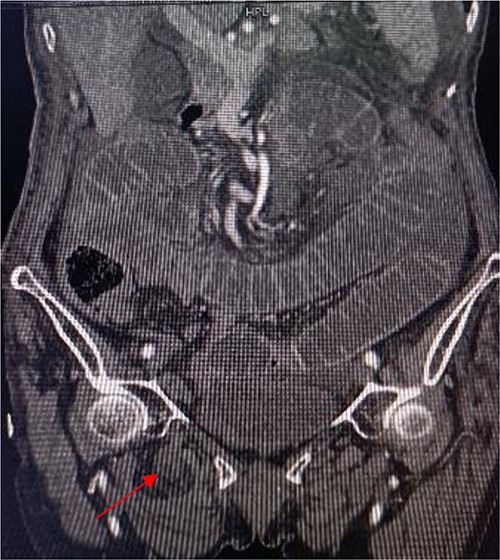

Coronal view shows right obturator hernia entering the intestinal canal (indicated by red arrow).